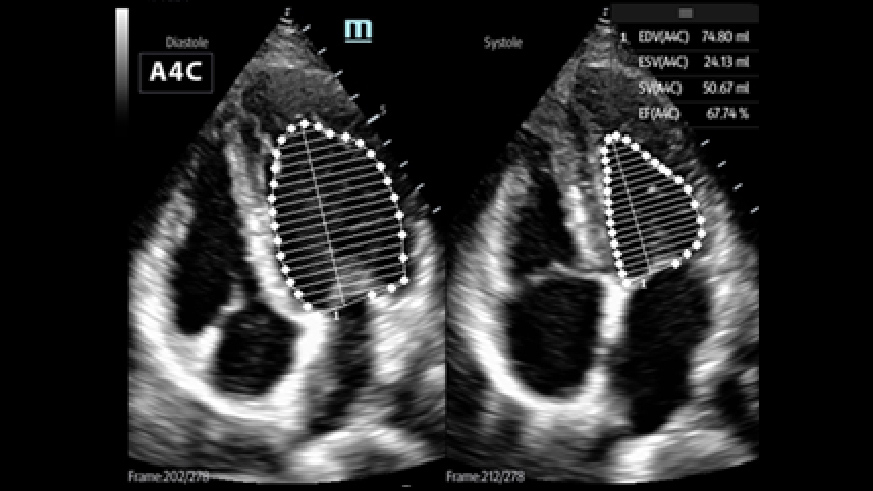

Critical Care Application

With exceptional cardiac imaging performance and advanced analysis tools, ME provides a combination of quality, efficiency and portability under critical care scenarios.

2Smart VTI

Automatic measurement of the VTI (Velocity Time Integral) and CO (Cardiac Output), for rapid assessment of cardiac function. Automatically locate color box and PW sample line on real time. A graph of parameters trends about CO, SV and VTI to guide the decision-making.